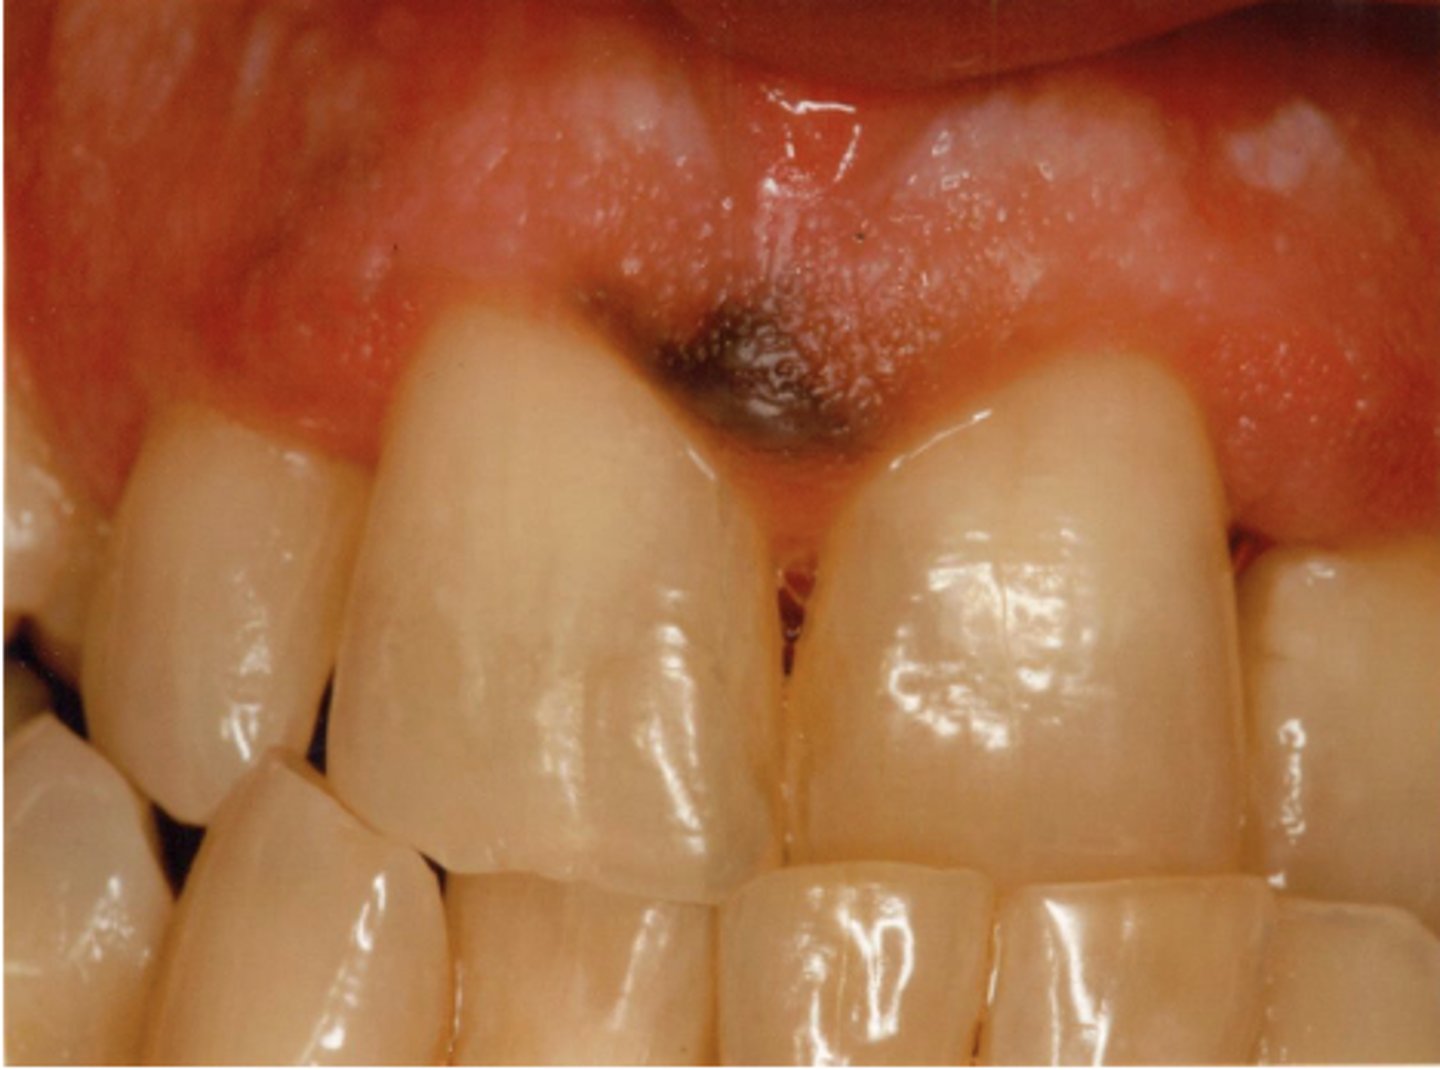

What type of pigmented lesion?

amalgam tattoo

These are clinical features of what?

- Asymptomatic, localized

- Blue-gray macule

- Localized around areas with amalgam restorations

amalgam tattoos

What is the most common location of amalgam tattoos?

gingiva/alveolar ridge mucosa (50%, then buccal mucosa, then floor of mouth)